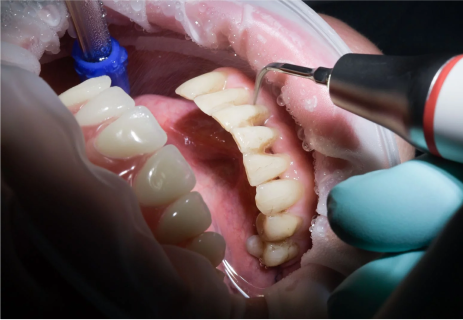

etapy leczenia implantologicznego

Leczenie implantologiczne jest procesem wieloetapowym. Czas potrzebny do jego zakończenia uzależniony jest od sytuacji klinicznej oraz od przebiegu procesów fizjologicznych w organizmie pacjenta. Standardowo wykonywany jest zgodnie ze schematem.

część chirurgiczna

ISTOTNE ELEMENTY LECZENIA

- W trakcie wgajania się implantu wymagane są wizyty kontrolne w gabinecie w odstępach cotygodniowych do zdjęcia szwów po zabiegu, a następnie comiesięcznych do odsłonięcia implantu.

- Przedstawiony powyżej schemat leczenia może ulegać zmianom technicznym i czasowym.

- W zależności od warunków kostnych u pacjenta oraz technicznego planu implantacji możliwe jest natychmiastowe osadzenie korony protetycznej na implancie zaraz po jego wszczepieniu. Taka sytuacja kliniczna określana jest jako natychmiastowe obciążenie implantu.

- W obecności trudnych warunków kostnych może zaistnieć konieczność wykonania zabiegów dodatkowych, takich jak odbudowa kości, które mogą wydłużyć czas wgajania implantów lub rozciągnąć cały proces o dodatkowe etapy.

- Istnieje cały szereg dodatkowych zabiegów rekonstrukcyjnych, dzięki którym w sytuacji istniejących trudności można stworzyć prawidłowe warunki dla wprowadzenia implantu. Zabiegi te określane są jako regeneracja kości

- W sytuacji ekstremalnie trudnych warunków kostnych leczenie implantologiczne ulega pierwotnej modyfikacji o niestandardowe rozwiązania, jakimi są np. implanty zygomatyczne.

- W trakcie osteointegracji implantów pacjent użytkuje tymczasowe uzupełnienia protetyczne, które zabezpieczają mu w stopniu podstawowym wymogi funkcjonalne i estetyczne.

część protetyczna